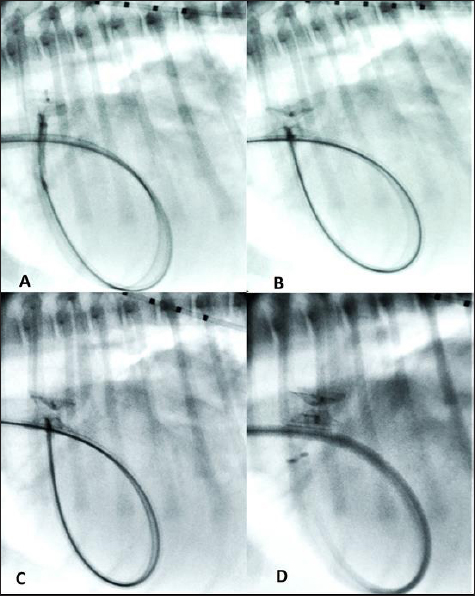

Fig. 2. Transthoracic echocardiographic (right parasternal short axis view, optimized for duct visualization). (A) PDA visualization and its measurement and (B) left to right flow on CFM Doppler (dual mode).

Thoracic radiographs showed left-sided cardiomegaly and pulmonary over circulation (Fig. 1). A transthoracic echocardiogram revealed severe left atrial and left ventricular dilation: left atrium/aorta (LA:Ao): 2.04, reference value: <1.6, normalized left ventricular internal diastolic diameter (LVIDDN): 3.02, reference value: ≤1.7) and large PDA, with an approximate minimal ostium and ampulla diameters of 5.2 and 10.3 mm (Fig. 2). Doppler echocardiography confirmed left-to-right flow across the PDA with a pressure gradient of 102 mmHg in systole and 41 mmHg in diastole. Mild mitral regurgitation was also noted.

Fig. 3. (A) Fluoroscopic sequence after the AVP II first disc has been released engaging the aortic side of the PDA and the central part left unsheated and (B) subsequently the other second component has been deployed an immediate “pull-through” into the pulmonary artery occurred immediately after to deployment of the whole device